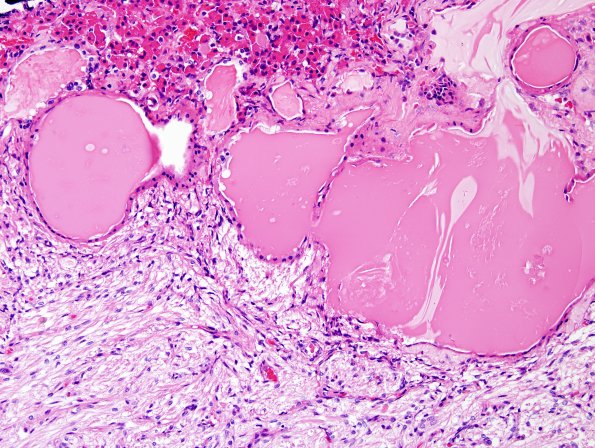

The intermediate lobe consists of many small epithelium lined cysts in this case which are thought to represent the residua of Rathke’s pouch. (H&E)